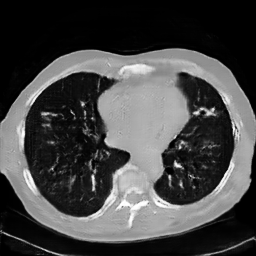

The study utilizes three 3D datasets, namely the GSP dataset[3], the LIDC-IDRI dataset[1], and the dataset employed for the Lung Nodule Analysis 2016 (LUNA16) challenge[21] which is a subset of LIDC-IDRI dataset. Samples from generated images at different stages of training are presented in Fig. 2 and Fig.3.

Figure 3: Synthetic images of CRF-GAN and HA-GAN at different iterations of training on the LUNA16 dataset